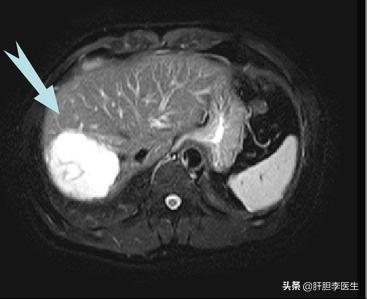

这次来复查的时候,直接做了肝脏的增强核磁,虽然知道血管瘤会增大,但是没想到看到片子的时候还是有点出乎意料,血管瘤的最大直径已经达到了17cm,几乎右边的肝脏都是血管瘤了,只剩下左边半个肝脏在维持正常工作了。当然手术的风险并不止这一点,而是血管瘤紧紧地贴在下腔静脉上,手术切除血管瘤就要把血管瘤从下腔静脉上一点一点地扒下来,在这个过程中随时有可能出现大出血的情况,而且下腔静脉的出血非常凶险,可能会有生命危险。